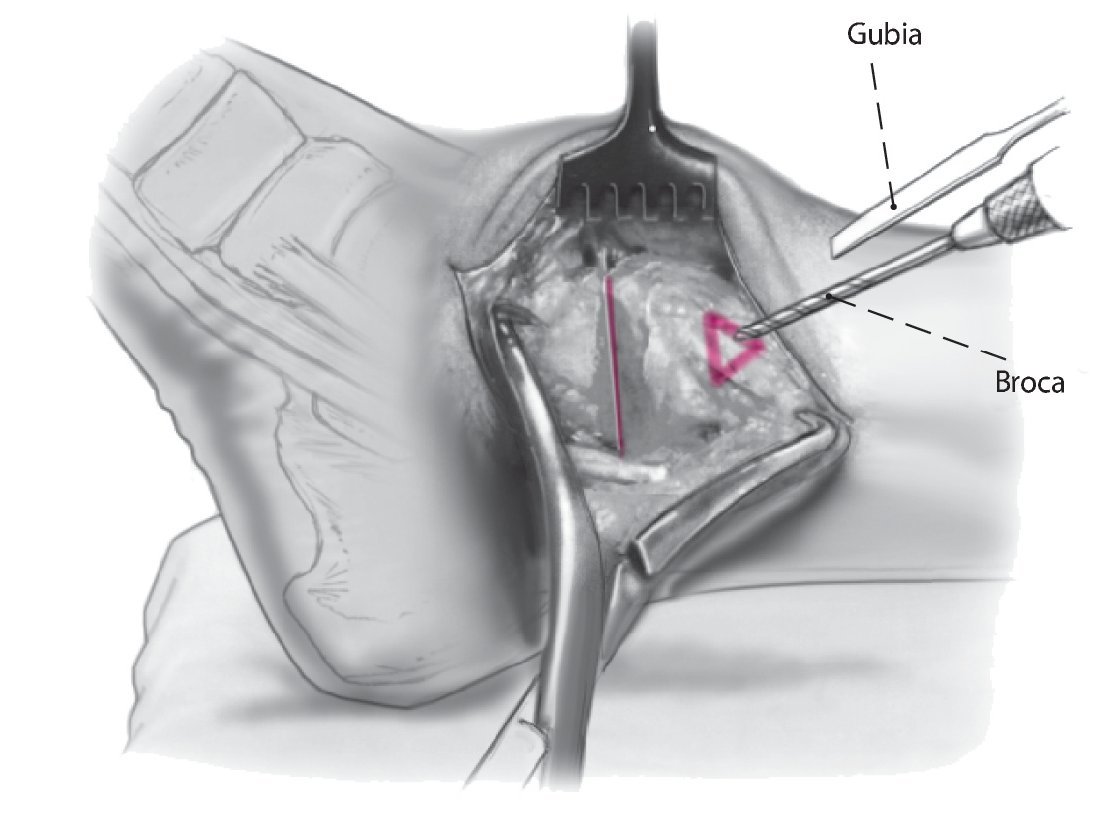

Fig. 10 Utilice la broca de 2,5 mm y un gubia de 1 cm para extraer un triángulo de capa cortical en el lado anteromedial de la tibia. La base del triángulo debe ser paralela a la planta del pie. Eso permite el avellanado, así como un posicionamiento más pendiente del tornillo respecto a la tibia.

Fig. 11 Mediante el uso de una broca de deslizamiento/broca guía de 4,5 mm se realizan agujeros en sentido medial y lateral, seguidos de agujeros de 3,2 mm con rosca en la capa cortical opuesta. Se colocan dos tornillos corticales de fijación de 4,5 mm con rosca completa y arandelas. El tornillo medial se dirige un poco en dirección anterior, mientras que el tornillo lateral se orienta ligeramente más posterior. Lo ideal es que el tornillo cruce craneal al nivel de la osteotomía.